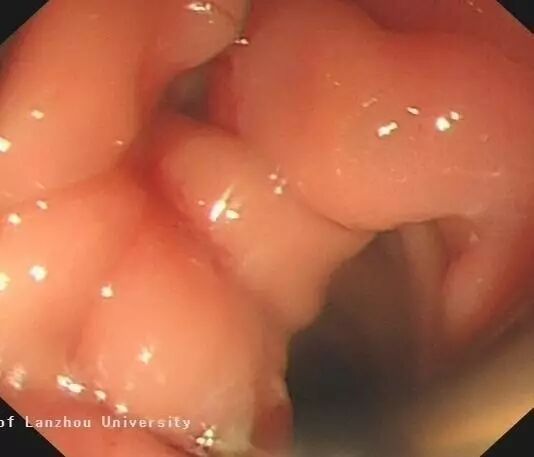

胃5cm间质瘤ESD创面

瘤体大约3*5cm,创面大约在6-7cm;2月后复查胃镜,OTSC夹及内镜夹仍在原位,缺损面已由新组织生长完全(最后图)